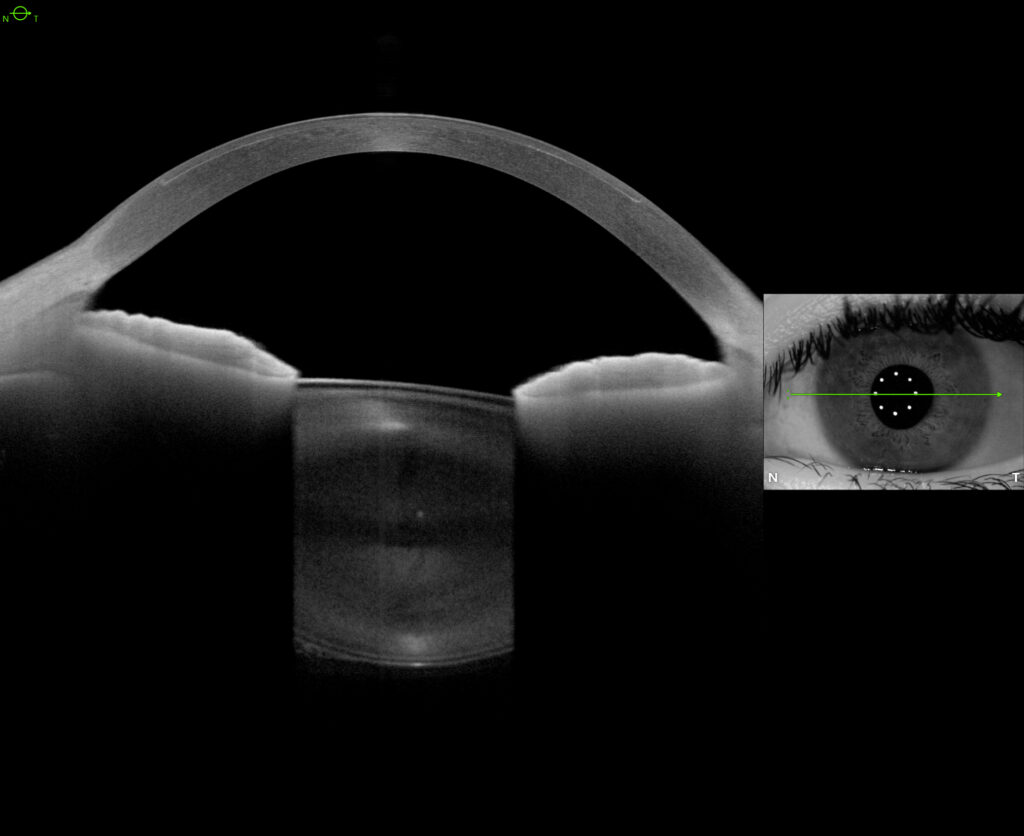

- Flaps are constructed using either a mechanical microkeratome or a femtosecond laser. Regardless of the instrumentation, a thin flap corneal flap, measuring approximately 100 microns in thickness, is created. The excimer laser is then applied to the corneal stromal tissue under this flap.

- While modern mechanical microkeratome are excellent, the femtosecond laser (Z4) has become our preferred technique for flap creation. This is commonly called All-Laser LASIK or Bladeless LASIK.

The Ziemer Z4 enables near perfect flap positioning, exact control of flap thickness, maximization of the flap diameter, customization of the flap shape, and selection of the hinge location. This enhances safety, maximizes corneal stability, optimizes visual quality, and reduces dry eye.